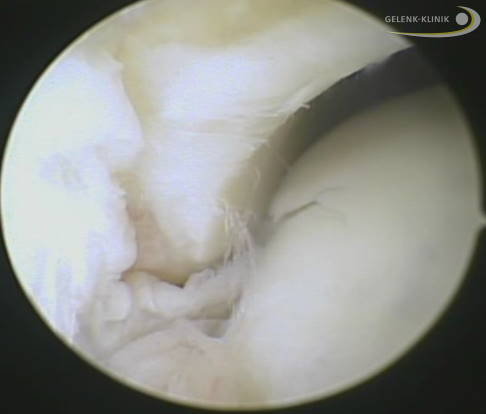

Knorpelschäden teilt der Arzt in vier Schweregrade entsprechend der Klassifikation nach Outerbridge ein.

- Grad 0: Der Knorpel ist glatt glänzend und bei der Beurteilung mit dem Tasthaken stabil (Normalbefund).

- Grad 1: Der Knorpel ist glatt, gibt bei Druck aber nach.

- Grad 2: Der Knorpel ist oberflächlich aufgefasert.

- Grad 3: Der Knorpel ist aufgerissen bis auf die darunterliegende Knochenlamelle.

- Grad 4: Der großflächige Knorpelverlust reicht bis auf den Knochen.

Mikrofrakturierung bei Knorpelschaden am Sprunggelenk

Eine bewährte Technik zur Regeneration des Knorpels im Sprunggelenk ist die Mikrofrakturierung. Dabei wird der unter dem Knorpeldefekt liegende Knochen mit einer Stanze bearbeitet, sodass minimale Einrisse im Knochen entstehen (Mikrofrakturen). Durch die Knochenverletzung kommt es zur Einblutung, dabei strömen Stammzellen aus dem Blut in die defekte Knorpelfläche. Diese Stammzellen differenzieren sich nach einigen Wochen zu Faserknorpel. Der Faserknorpel ist nicht ganz so robust wie der ursprüngliche hyaline Knorpel, erfüllt seinen Zweck zur Auffüllung der Knorpelfläche dennoch sehr gut.